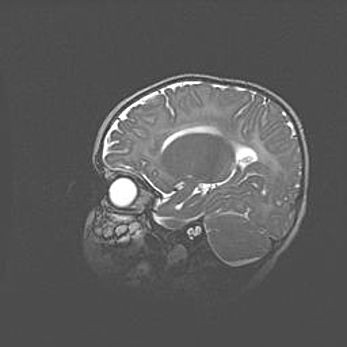

Мальформация Денди-Уокера. Киста задней черепной ямки.

Агенезия мозолистого тела.

Возраст: 2,5 месяца

Вес: 2420 г

Пол: женский

Окружность головы: 37 см

Срок гестации: 32 недели

Мальформация Денди—Уокера — редкий вид патологии ЦНС, представляющий собой врожденный порок развития каудального отдела ствола и червя мозжечка, ведущий к неполному раскрытию срединной (Мажанди) и латеральных (Лушка) апертур IV желудочка мозга. Для этогно синдрома характерна триада симптомов: гипотрофия червя мозжечка и/или полушарий мозжечка, кисты задней черепной ямки, гидроцефалия различной степени. В 70% случаев порок сочетается и с другими аномалиями головного мозга, в частности с агенезией мозолистого тела.